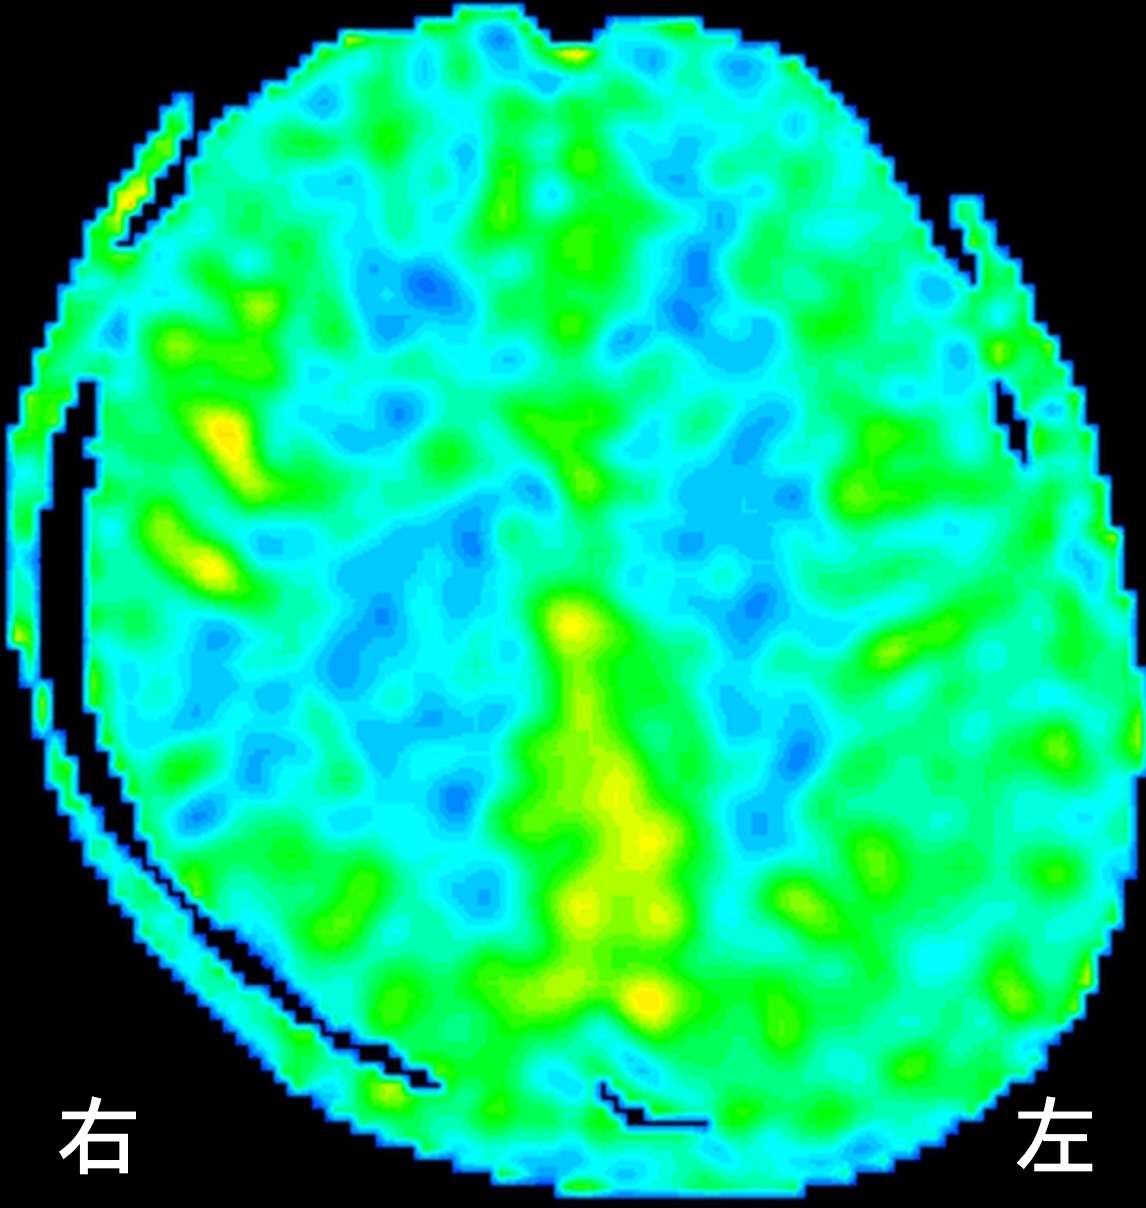

ASL後期

徐々に血流が補われていく状態がうかがえます。